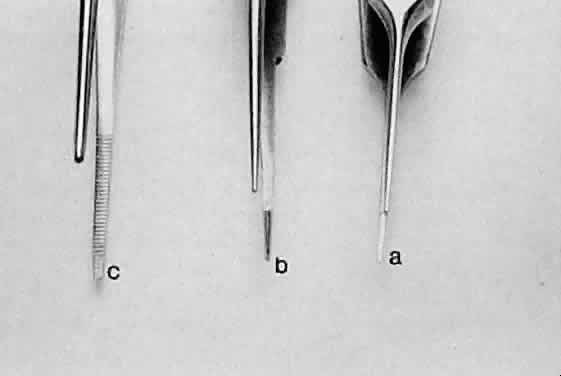

GRASPING TISSUE Before using a forceps to grasp tissue, the surgeon must have a clear understanding

forceps, and the spatula (the hook). Smooth forceps (i.e., forceps without teeth) must be used when handling

delicate tissues (Fig. 15). For example, smooth forceps are necessary when working with tissue that

must not be punctured or damaged, such as the conjunctiva during a

trabeculectomy. An absolutely smooth forceps with no defined grasping

surface usually is ineffective when handling the conjunctiva. Such a

forceps (also called a tying forceps)—is—used to hold fine

suture. Instead, serration of the grasping surface provides increased

friction without damaging the tissue. It is effective in handling the

conjunctiva because the conjunctival surface can conform to the ridges

of the serration. Criss-cross serrations permit traction in all directions. If

one attempts to use a serrated forceps on rigid material, such

as the sclera, only the tips of the serration will hold the tissue, reducing

the contact area and the effectiveness of the forceps (Fig. 16). Therefore, toothed forceps must be used to grasp the sclera effectively.  Fig. 15. Three different smooth forceps. On the right is an absolutely smooth forceps (A). In the middle is a grooved forceps (B). On the left is an instrument with a serrated platform (C). The instrument on the right is used to grasp fine suture, whereas the

instrument on the left is more commonly used to handle conjunctiva or

thin tissue that can conform to the ridges of the serration. Fig. 15. Three different smooth forceps. On the right is an absolutely smooth forceps (A). In the middle is a grooved forceps (B). On the left is an instrument with a serrated platform (C). The instrument on the right is used to grasp fine suture, whereas the

instrument on the left is more commonly used to handle conjunctiva or

thin tissue that can conform to the ridges of the serration.